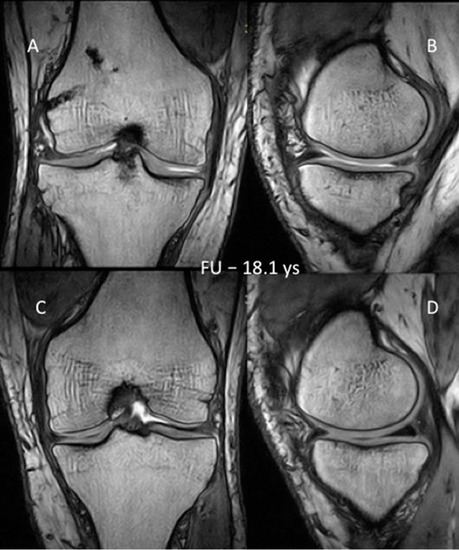

3.3. MRI Evaluation of the Cartilage

- Meglic, U.; Salapura, V.; Zupanc, O. MRI Findings of Early Osteoarthritis in Patients Who Sustained Septic Arthritis of the Knee After ACL Reconstruction. Orthop. J. Sports Med. 2021, 9, 23259671211052519. [Google Scholar] [CrossRef] [PubMed]

| 18.1-years | SG | 2.217 | 0.63 | 3.99 | 0.725 | 0.043 ** | |

| CG | 2.43 | 0.58 | 4.9 | 0.87 | |||